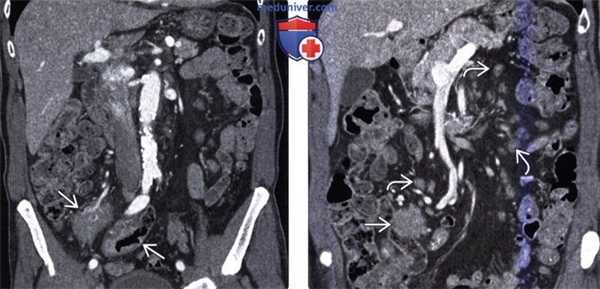

Гематогенное метастазирование в тонкую кишку из очага первичного печеночно-клеточного рака у пациента 63 лет с анемией.

(а) При КТ в коронарной проекции в тонкой кишке визуализируется округлое гиперваскуляризованное полиповидное образование (стрелки). Отмечается кишечно-кишечная инвагинация, обусловленная метастатическим поражением тонкой кишки.

(б) Фотография макропрепарата: три полиповидных новообразования с центральным изъязвлением. Метастазы в тонкой кишке у мужчины 63 лет, которому год тому назад выполнена правосторонняя гемиколэктомия по поводу рака ободочной кишки.

При КТ в коронарной проекции визуализируется поражающая брюшину опухоль (стрелка), сдавливающая петлю тонкой кишки и вызывающая непроходимость.

Отмечаются наполненные жидкостью расширенные петли тонкой кишки и «симптом фекалий в тонкой кишке» (звездочка).

На пораженной брюшине выявляются множественные узелки (указатели).